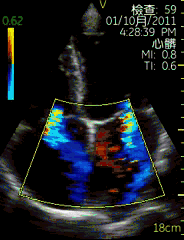

| 心尖四腔切面(彩色) | | 介绍重点: | 心脏各腔室大小正常、瓣膜运动协调; |

| 左房增大,二尖瓣启闭受限; |

| 左房增大,二尖瓣舒张期前向血流速度增快,收缩期可见蓝色反向血流; | | 临床用途: | 评估心脏各腔室大小,瓣膜结构与功能;(正常图像) |

| 风湿性心脏病:二尖瓣狭窄伴关闭不全; |

心尖四腔切面

| 图像名称: | 心尖四腔切面(彩色) |

| 心尖四腔切面(彩色) | | 介绍重点: | 房室瓣彩色多普勒显示有心房到心室的单向红色血流 |

| 心尖四腔切面(彩色) | | 介绍重点: | 收缩期源于二尖瓣口的蓝色反流束 |

| 右房内偏向房间隔的的蓝色反流束 | | 临床用途: | 二尖瓣关闭不全 |

| 三尖瓣关闭不全 |